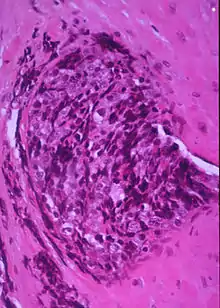

In histopathology, a small-blue-round-cell tumour (abbreviated SBRCT), also known as a small-round-blue-cell tumor (SRBCT) or a small-round-cell tumour (SRCT), is any one of a group of malignant neoplasms that have a characteristic appearance under the microscope, i.e. consisting of small round cells that stain blue on routine H&E stained sections.

These tumors are seen more often in children than in adults. They typically represent undifferentiated cells. The predominance of blue staining is because the cells consist predominantly of nucleus, thus they have scant cytoplasm.[1][2]